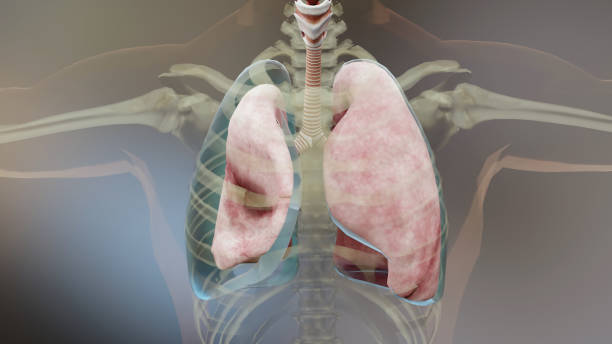

기흉(pneumothorax)은 폐와 흉부벽 사이에 공기가 쌓이는 상태를 말합니다. 이는 폐가 공기로 가득 차면서 폐가 축소되고 압축되어 발생합니다. 이러한 압축으로 인해 폐의 기능이 저하되며 호흡 곤란, 가슴 통증 등의 증상을 유발할 수 있습니다.

기흉은 크게 외상성 기흉과 비외상성 기흉으로 나눌 수 있습니다. 외상성 기흉은 외상이나 사고 등으로 인해 폐에 손상이 생기거나 뚫리면서 공기가 쌓이는 것이며, 비외상성 기흉은 폐의 질환으로 인해 공기가 쌓이는 것입니다. 비외상성 기흉은 폐기종증, 천식 등 다양한 원인에 의해 발생할 수 있습니다.